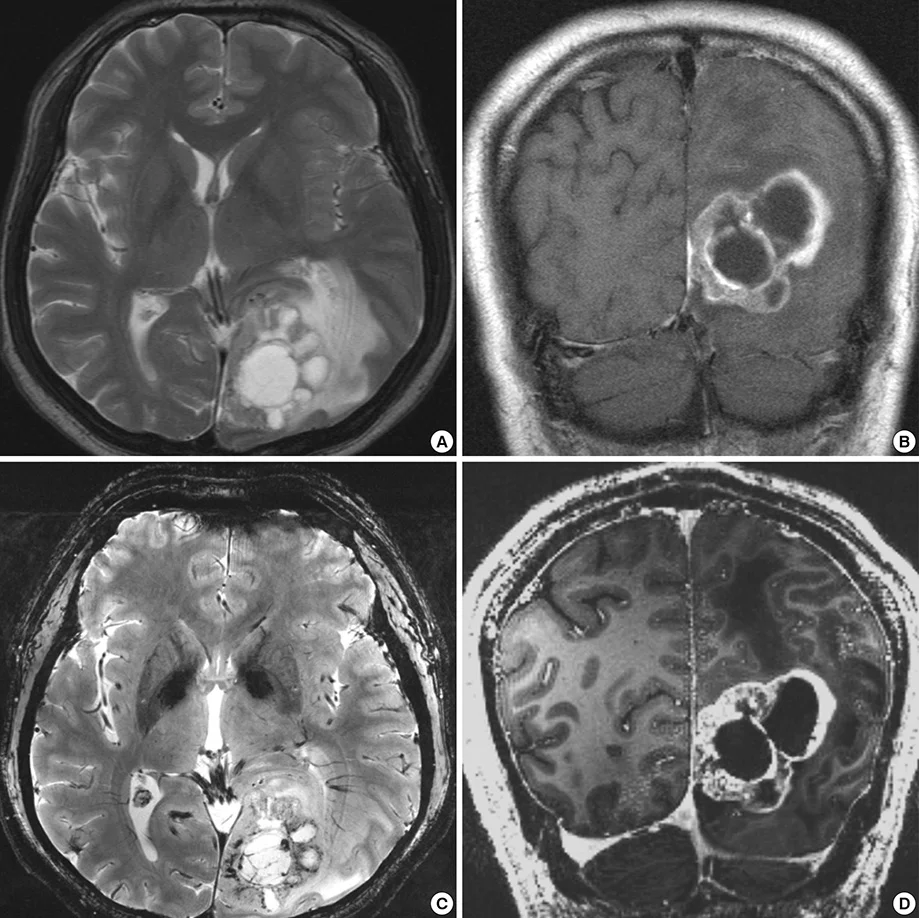

- MRI υψηλής ανάλυσης

Η διάγνωση ξεκινά σχεδόν πάντα με μαγνητική τομογραφία (MRI) εγκεφάλου ή σπονδυλικής στήλης. Στη συνέχεια, συνδυάζουμε τα ευρήματα με το ιστορικό και τη νευρολογική εξέταση, ώστε να διαμορφώσουμε μια ασφαλή θεραπευτική στρατηγική.

- MRI υψηλής ανάλυσης, με ειδικά πρωτόκολλα όπου χρειάζεται (perfusion / spectroscopy).

Εξειδικευμένη αξιολόγηση MRI

Ανάλυση εικόνων, νευρολογική εξέταση, εκτίμηση κινδύνου.